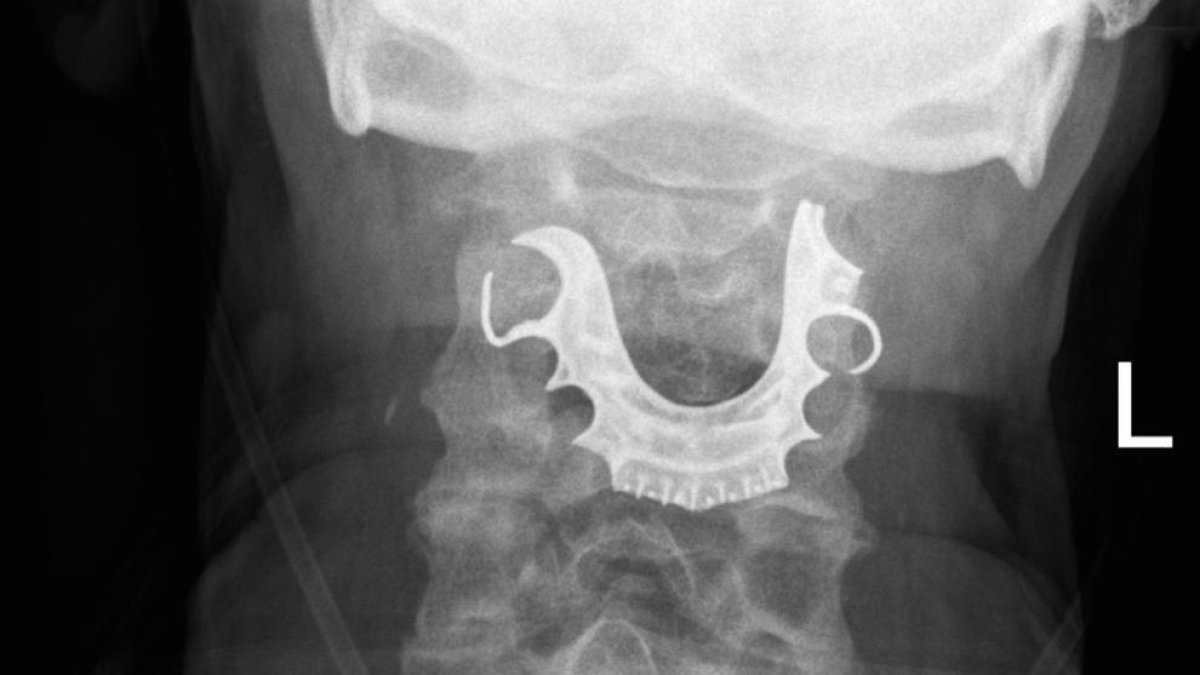

Un home de 72 anys va acudir a urgències al Regne Unit per un fort dolor a la faringe. Quan li van fer una radiografia van descobrir que el pacient tenia la seva dentadura postissaclavada a la seva gola.

La dentadura va acabar a la seva faringe després de sotmetre's a una operació per extreure un bonydel seu abdòmen, segons ha informat BMJ Case Reports. Es creu que el pacient se la va tragar al ser anestesiat, fet que li ha provocat nombroses ampolles internes i una gran inflamació.

Al no trobar milloria, l'home va tornar i va ser quan li van fer més proves i van descobrir que tenia la dentadura a la gola. El pacient va explicar que durant l'operació havia perdut les seves peces bucals. Finalment, va ser operat d'urgència per extreure-li. Dies després, va ser intervingut un altre cop per aturar el sangrat d'una arteria, provocat per les hemorràgies anteriors.